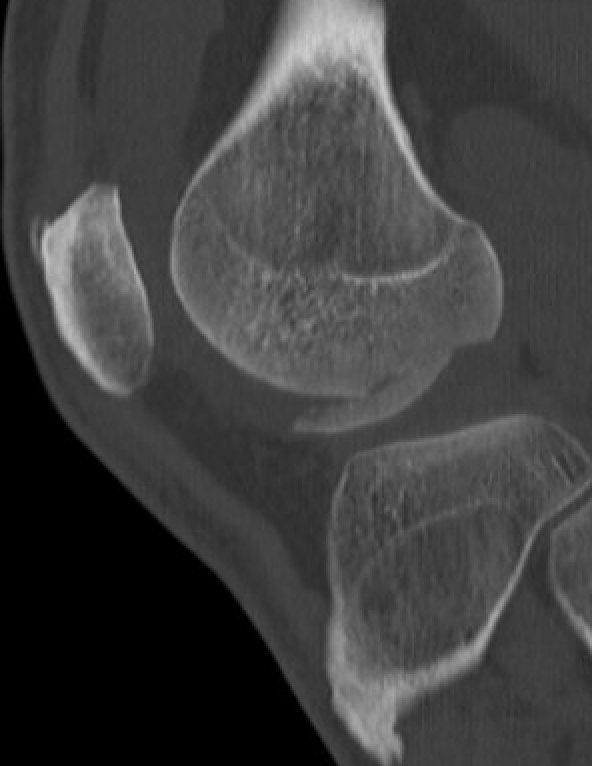

CT

Osteochondral fracture of the lateral femoral condyle

Large osteochondral fracture medial facet patella

Large osteochondral fracture lateral femoral condyle